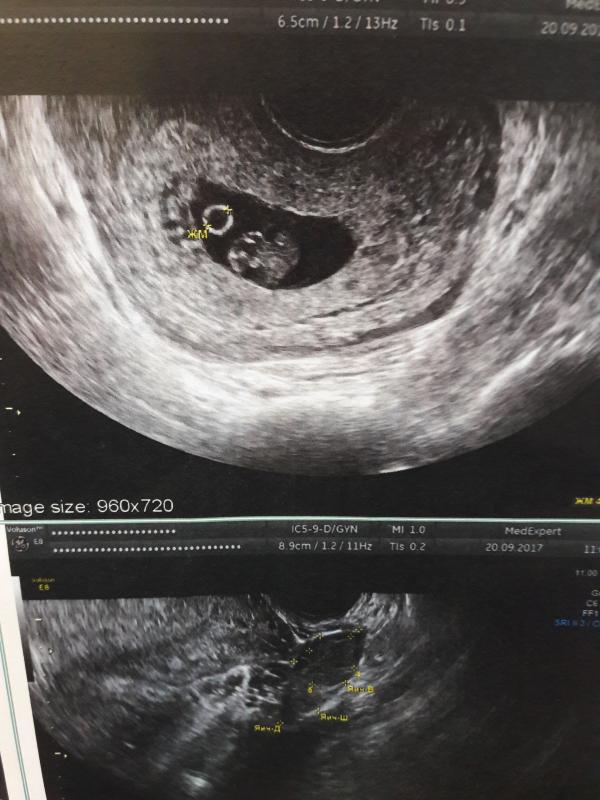

Ну что ж, сходила на узи и рада как слон. Все хорошо. Ктр 18мм. За 10 дней вырос с 1.6мм. Поставили 8.4 недели, она сказала что как раз от зачатия. И как я поняла ставят эмбриональный срок. Теперь вопросик. Она не сказала по какой стенке прикрепление. Если кто понимает может определить по какой стенке?

8,4 - это по акушерскому сроку) По УЗИ всегда говорят лишь акушерский срок, аппараты так автоматом считают) да и по табличкам всем у Вас ктр ровно на 8 недель и пару дней))) Растите и развивайтесь ☺️🙏🏻

Всегда в результатах узи пишут «хорион по такой-то стенке», во все беременности делала узи в 6-7 недель и в заключении обязательно была информация о прикреплении. Не знаю, почему в вашем заключении такого нет(

@linya-yle, на первом скрининге вам напишут где прикрепление, сейчас ещё рано, на УЗИ вашем об этом не написано))))